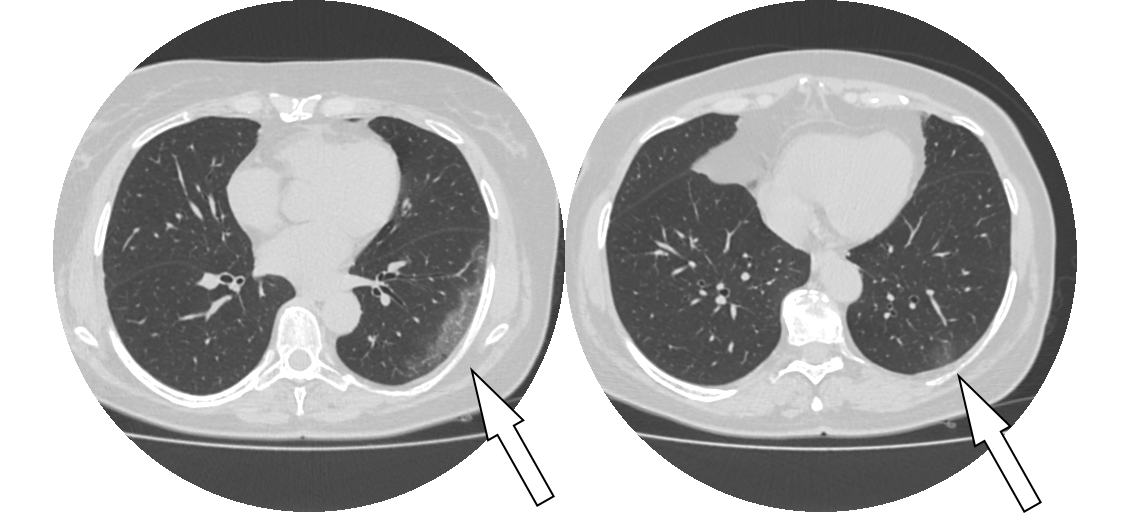

模型检测效果如下图:

对预测结果进行展示

可见模型对磨玻璃样病灶的细节分割并不是很好。但是这个项目的目地只是需要通过预测的mask结果在原图上画出病灶的轮廓,实现对病灶的检测和定位。告诉医疗那一层有磨玻璃样病灶,或者告诉医生那一层出现的磨玻璃样病灶面积是最大的。

对整个医疗数据图像文件Nifit文件进行推理

医学影像数据,一般是Nifit格式或者Dicom格式。是一种三维数据。因为训练过程中采用2D数据训练。最后对医疗影像数据进行推理时,需要一层层进行推理,并把最后结果再堆叠组合成三维数据。